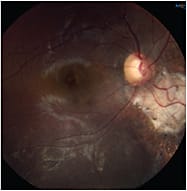

|

| Q. Is this an equipment operational problem? | A. Possibly; the camera may not be in alignment. |

| Q. What troubleshooting is needed for the camera? | A. Manipulate the camera angle to overcome this problem. |

| Q. Is there pathology present? | A. Yes. An elevated chorioretinal scar. |

| Q. What aberrations/artifacts are included and how do you correct them? | A. Lid artifact is present. If it was the iris, the artifact would be a bluish tint. A white crescent around the picture indicates the camera is too far away and not in focus. |

| COURTESY STEPHANIE D. MCMILLAN, MHA, COA | |